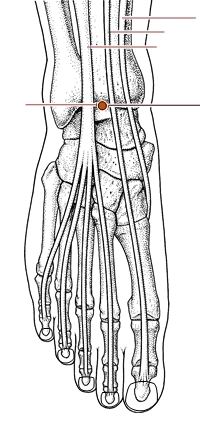

解溪穴

经穴名。出《灵枢·本输》。别名草鞋带。属足阳明胃经。经(火)穴。在足背与小腿交界处的横纹中央凹陷中,当拇长伸肌腱与趾长伸肌腱之间。布有腓浅神经,腓深神经和胫前动、静脉。主治头痛,眩晕,目赤,腹胀,便秘,癫狂,头面浮肿,下肢痿痹,脚腕无力等。直刺0.3-0.5寸。艾条灸5-10分钟。